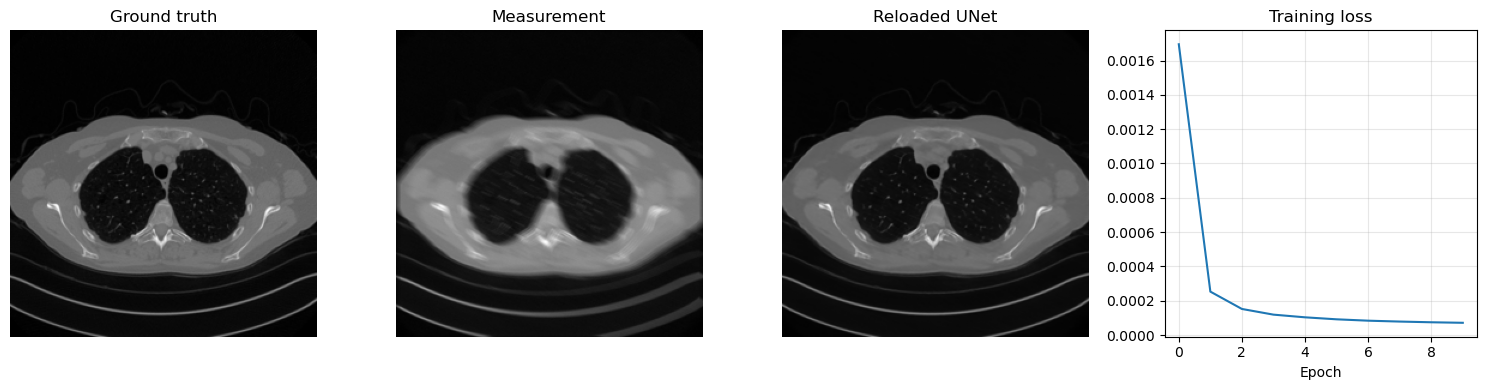

Training a residual model follows exactly the same logic as for the plain CNN, but now the network learns a correction to be added back to the corrupted input. The code below trains a ResCNN for 50 epochs on the Mayo motion-blur task, saves the learned parameters in ../weights/ResCNN.pth, reloads them, and visualizes one reconstruction together with the loss history.

plt.figure(figsize=(15, 4))

plt.subplot(1, 4, 1)

plt.imshow(x_true.cpu().squeeze(), cmap='gray')

plt.title('Ground truth')

plt.axis('off')

plt.subplot(1, 4, 2)

plt.imshow(y_delta.cpu().squeeze(), cmap='gray')

plt.title('Measurement')

plt.subplot(1, 4, 3)

plt.imshow(x_rec.cpu().squeeze(), cmap='gray')

plt.title('Reloaded UNet')

plt.subplot(1, 4, 4)

plt.plot(unet_history)

plt.title('Training loss')

plt.xlabel('Epoch')

plt.grid(alpha=0.3)

plt.tight_layout()

plt.show()

Epoch 1/10: 100%|██████████| 414/414 [16:31<00:00,  2.40s/it, avg_loss=0.001695, batch_loss=0.000446]

Epoch 2/10: 100%|██████████| 414/414 [16:29<00:00,  2.39s/it, avg_loss=0.000253, batch_loss=0.000196]

Epoch 3/10: 100%|██████████| 414/414 [15:45<00:00,  2.28s/it, avg_loss=0.000152, batch_loss=0.000106]

Epoch 4/10: 100%|██████████| 414/414 [15:39<00:00,  2.27s/it, avg_loss=0.000119, batch_loss=0.000084]

Epoch 5/10: 100%|██████████| 414/414 [15:38<00:00,  2.27s/it, avg_loss=0.000104, batch_loss=0.000084]

Epoch 6/10: 100%|██████████| 414/414 [15:32<00:00,  2.25s/it, avg_loss=0.000092, batch_loss=0.000088]

Epoch 7/10: 100%|██████████| 414/414 [15:45<00:00,  2.28s/it, avg_loss=0.000084, batch_loss=0.000082]

Epoch 8/10: 100%|██████████| 414/414 [16:19<00:00,  2.37s/it, avg_loss=0.000079, batch_loss=0.000073]

Epoch 9/10: 100%|██████████| 414/414 [16:02<00:00,  2.32s/it, avg_loss=0.000075, batch_loss=0.000086]

Epoch 10/10: 100%|██████████| 414/414 [16:07<00:00,  2.34s/it, avg_loss=0.000072, batch_loss=0.000057]

Saved weights to: C:\Users\tivog\computational-imaging\years\2025-26\weights\UNet.pth

Total trainable parameters: 1925025

../_images/8a4f99838d60b5ebba29782631fc22bdd5f07aa9018e47693bdedc6f887c7fe1.png